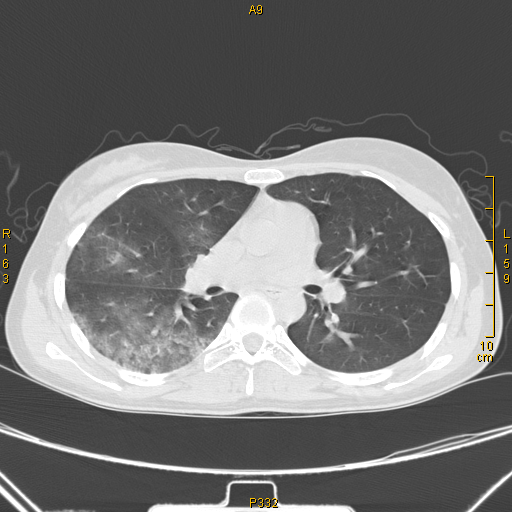

入院后行胸部ct检查提示双肺弥漫性炎症,表现为重症肺部感染.

肺部ct提示双下肺肺炎,右侧为著

或双肺多发的小斑片或磨玻璃密度影,形态各异,提示肺部感染性病变1

这是一个肺部感染合并心衰的胸部ct

这是一个新型冠状病毒感染病人的肺部ct